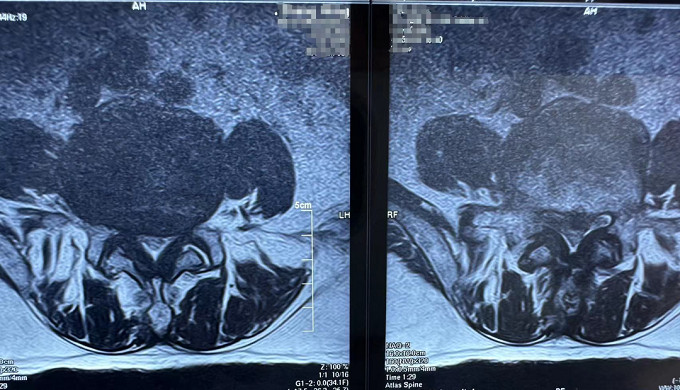

核磁共振(腰椎)

可以明顯的看出,患者術(shù)前椎間盤突出壓迫到了神經(jīng)。